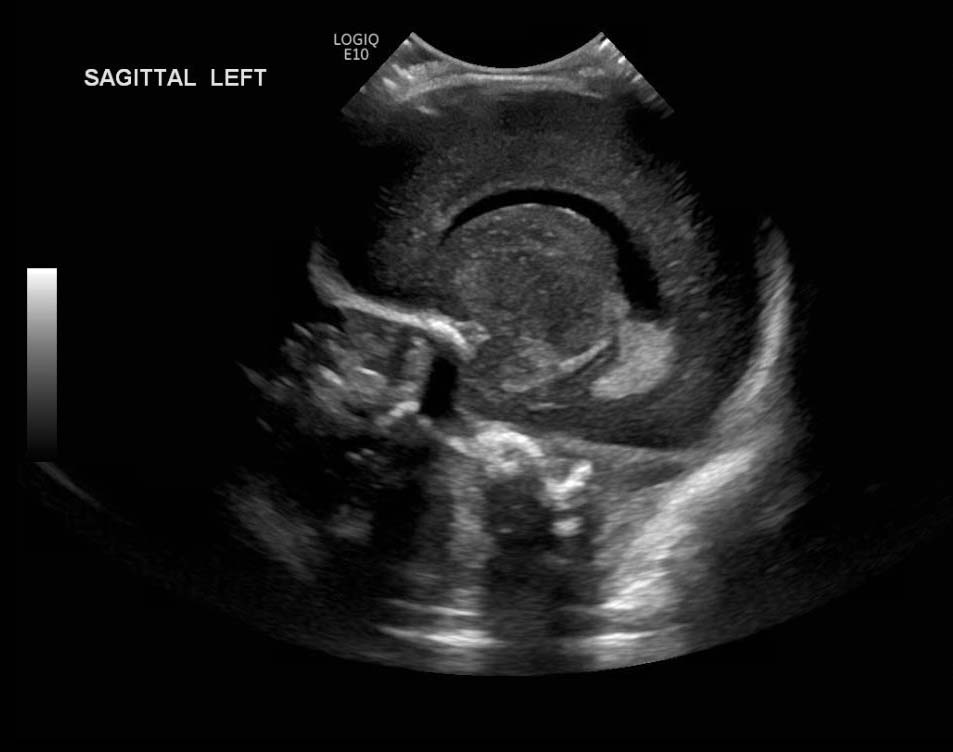

Age: 4 days (born at 24 weeks)

Sex: Male

Indication: Evaluate for germinal matrix hemorrhage

Grade 2 germinal matrix hemorrhage

Sample ReportLeft germinal matrix hemorrhage involving the caudothalamic groove and layering in the occipital horn of the left lateral ventricle without hydrocephalus (grade 2).

No abnormal brain parenchymal echogenicity or extra-axial collections.

Premature sulcation pattern.